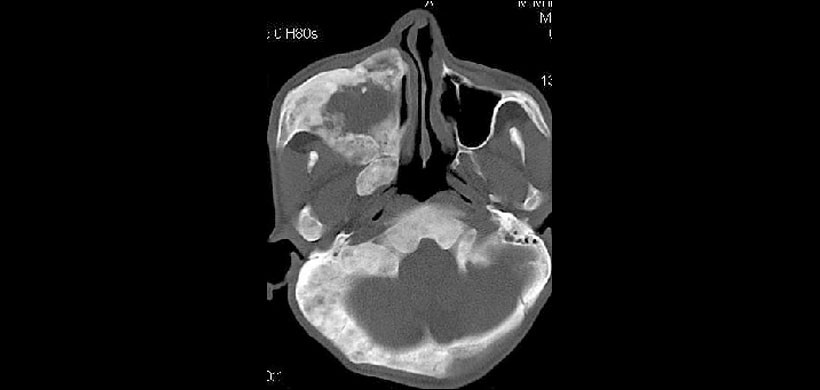

Figura 3: Corte axial de TC con ventana ósea que revela la participación de los huesos temporales, cigomáticos, frontales y etmoidales. El hueso esfenoidal también se ve comprometido e involucrado en el estrechamiento del canal óptico y en las fisuras orbitarias.